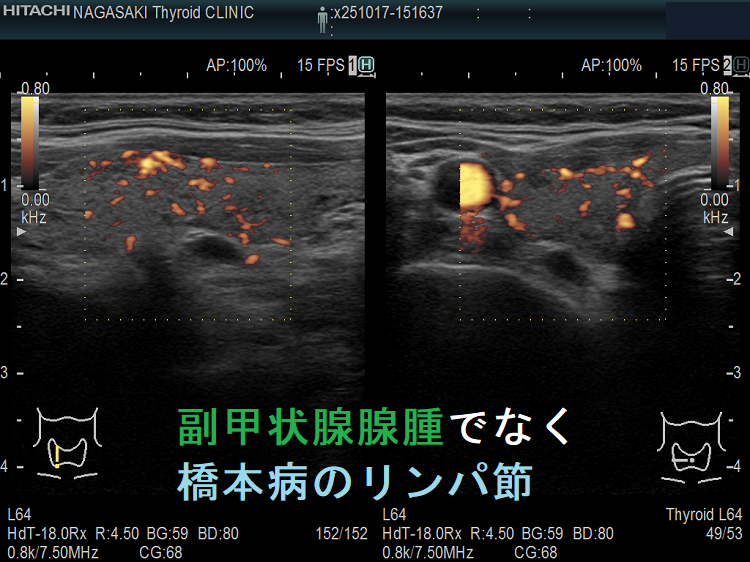

- 実はただのリンパ節、頚部異所性甲状腺、排液後縮小した甲状腺のう胞腺腫(甲状腺嚢胞腺腫)、甲状腺腺腫様結節

副甲状腺腺腫のように見えるも、実はただのリンパ節

副甲状腺腺腫との違いとして、リンパ節では

- 内部血流が無く

- リンパ門が存在します(ここだけ血流があります)

ケース③